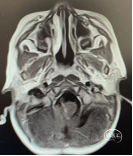

术前头部MRI

右侧桥小脑角区可见一不规则等T1、等-T2信号灶,大小约46*51*55mm3边界欠清,病灶突入四脑室内,第四脑室受压变窄,强化明显。